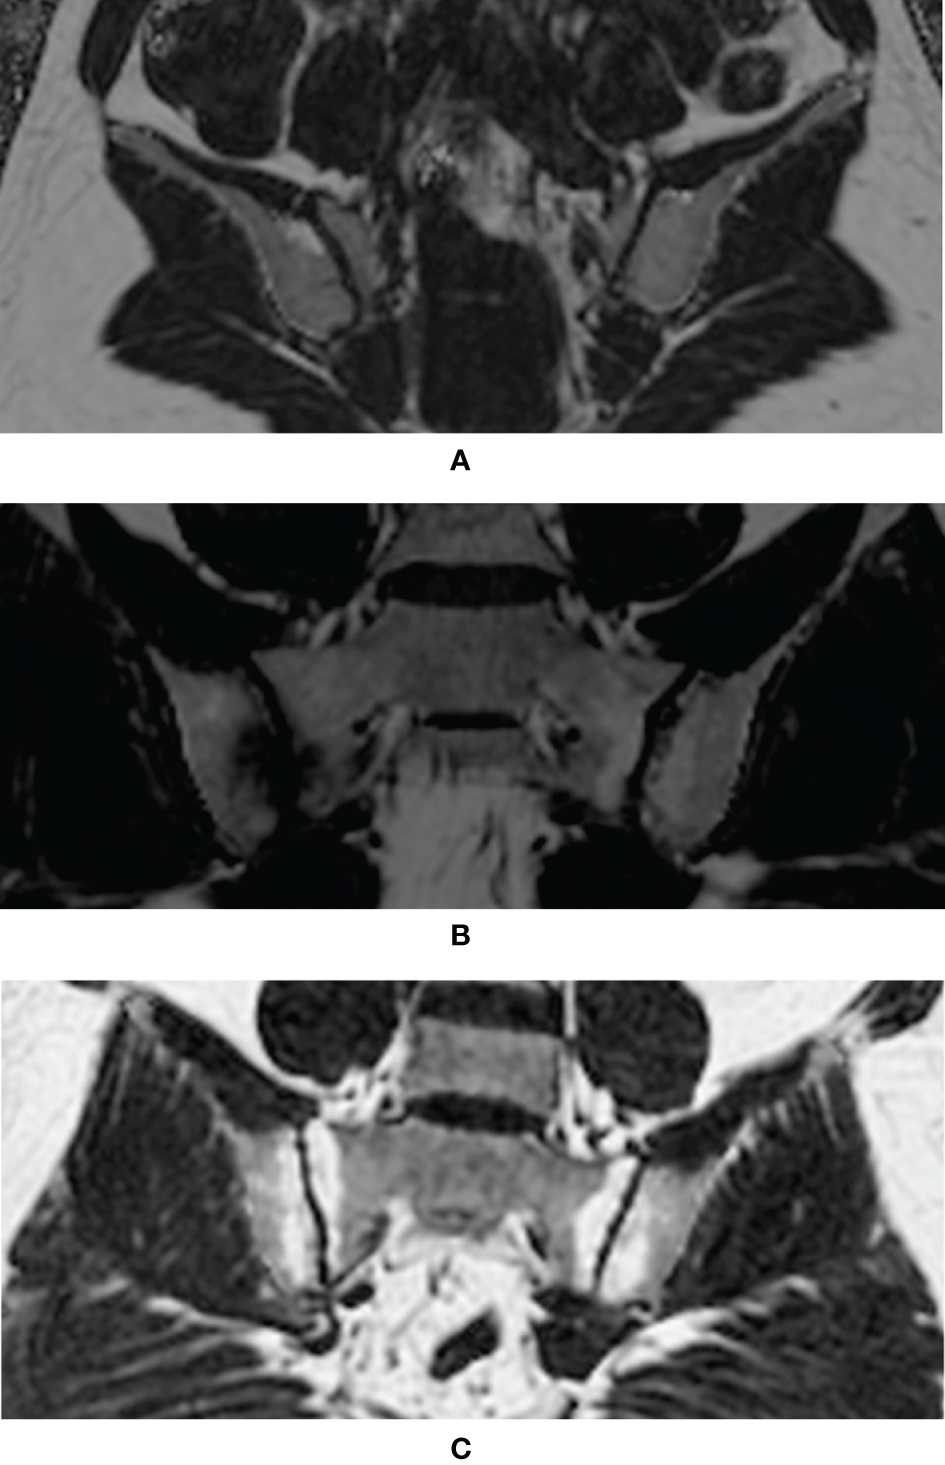

In order to estimate the fat fraction of each participant in the SIJs, the fat fraction maps were presented to each observer. Three consecutive slices most representative of the sacroiliac joint in the semi-coronal orientation were selected for the delineation of regions of interest (ROI). ROIs come in the shape of circles with sizes ranging from 10-40 mm2. Three ROIs were manually placed in the subchondral bone on both the left and right sacral side and iliac side (Figure 1). The overarching principle for ROI placement is that ROIs should be evenly distributed while capturing the extent of regional fat deposition. ROIs should stay clear of any erosion, blood vessel, cavity or obvious regional bone marrow edema. The mean PDFF values within the ROIs were generated automatically by the system.

Figure 1 Placement of ROIs in the subchondral area in the SIJs (ROI, regions of interest; SIJs, sacroiliac joints).

Figure 2 each displayed a typical example of the fat deposition pattern of: (A) Healthy volunteers with regional hot spots of fat deposition in the SIJ (B) SpA patients with simultaneous fat deposition and bone marrow edema in the SIJ (C) axSpA patients with fat deposition diffusely distributed in the subchondral area in the SIJ. Results of the comparative analysis of the differences of PDFF values among different groups were shown in Table 2.

Figure 2 Examples of typical fat deposition patterns in different diagnostic groups. (A) Healthy volunteers with regional hot spots of fat deposition in the SIJ (B) SpA patients with simultaneous fat deposition and bone marrow edema in the SIJ (C) axSpA patients with fat deposition diffusely distributed in the subchondral area in the SIJ (SpA, spondyloarthritis; axSpA, axial spondyloarthritis; SIJ, sacroiliac joint).

The CSE-MRI sequence is considered the state-of-the-art technique for the quantification of fat measurements (16). Its superiority to other fat quantification MR sequences, such as T1-in-and-out-of-phase (IOP) sequence, had been validated by a body of studies (17–19), even with evidence of histological analysis (23). Ren et al. led a preliminary effort to investigate CSE-MRI in the assessment of fat deposition in the SIJs of patients with ankylosing spondylitis (AS) (24). Yet, this study did not include patients without obvious structural damage on the radiographs, currently known as nr-axSpA, nor did it assess the incremental diagnostic values of fat fraction to BME, therefore alienating itself from daily clinical practice. A histographic study by Bray et al. established the connection between elevated PDFF values and the presence of fat metaplasia in the SIJs, thereby laying the foundation for our study (25). Our study was initiated from the daily clinical scenario, where patients complaining of back pain were classified as non-SpA, nr-axSpA and r-axSpA based on results of the diagnostic work-up. Results showed that the PDFF values in the SIJs of r-axSpA patients were significantly higher than the other three groups, which was in line with the previous study (24). On the other hand, the PDFF values in the SIJs of nr-axSpA patients, albeit lower than r-axSpA, were also significantly higher than the non-SpA group and healthy volunteers. An intriguing observation is that patients with axSpA exhibited different patterns of fat metaplasia in SIJs according to the fat fraction maps. For patients with long-standing sacroiliitis, fat deposition was often distributed in a diffuse fashion in the subchondral area in the SIJs (Figure 2C), leading to a high count of ROIs (PDFF>70%) (Figure 2C). Conversely, in some patients with acute sacroiliitis, due to the presence of intense bone marrow edema or osteitis, the PDFF values were lowered, while in other quadrants of the SIJs fat deposition was rather conspicuous (Figure 2B). This was also in line with the previous reports that fat deposition and acute bone marrow edema were mutually exclusive (26). Therefore, we held the opinion that the counts of ROIs with PDFF values over 70% might be a more reliable indicator than the overall mean PDFF values merely.